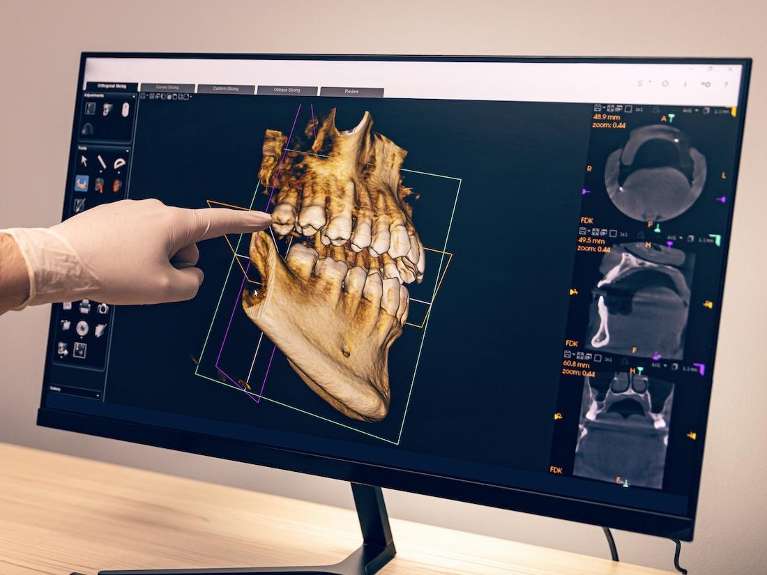

Structure of a Dental Implant

Dental implants are versatile and can replace single or multiple teeth. How it’s implanted will depends on your unique needs and the dentist’s recommendations.

A dental implant is made up of three main parts, the:

The implant post is a small titanium screw that your dentist surgically inserts into the jawbone. This post replaces the natural tooth root and provides a strong, permanent foundation for artificial teeth.

Over time, the bone fuses with the titanium to ensure long-term stability.